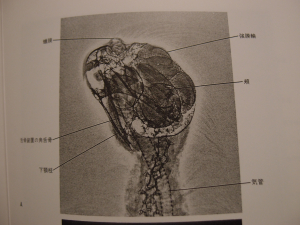

1997年に出版された本を、最近、買いました。12000円+税の本で、

20年前の写真でも、まぁ、いいか!とプラスに考えるようにしました(笑)

鳥の翼の画像が綺麗だな〜と思ったり、

オカメインコのX線の画像に

(正確にはX線ではなくゼロラジオグラフィというみたいです)、

冠羽がうっすらと映りこんでいる姿をみて、

それが可愛くて(笑)

つい盛り上がってしまって、衝動買いしました!

残念ながら、ヨウムもムラクモインコも

本のレパートリーには採用されていないのですが、

11種類の鳥のX線画像が、1羽に付き2〜4枚くらい載っています。

キソデ帽子インコ

オカメインコ

セキセイインコ

文鳥

オニオオハシ

ドバト

アカオノスリ

オオアメリカオオワシミミズク

マガモ

コリンウズラ

クロワカモメ

というレパートリーです。

でも、セキセイインコと、オカメインコの項目しか眺めていないので、

愛鳥贔屓だな〜と思う今日この頃です。